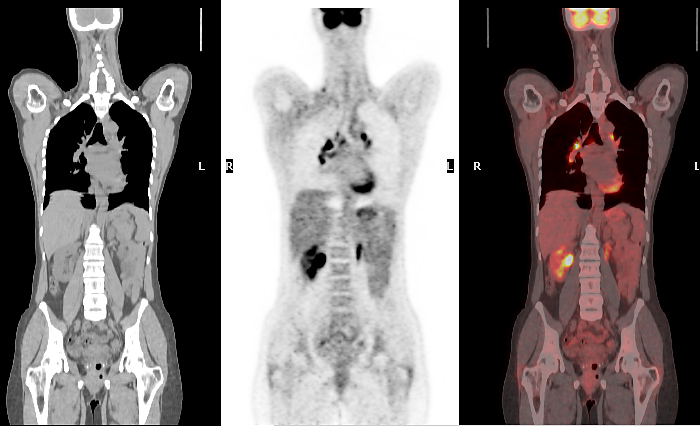

![[89Zr]Zr-girentuximab for PET–CT imaging of clear-cell renal cell ...](https://www.thelancet.com/cms/10.1016/S1470-2045(24)00402-9/asset/700721d8-bd15-46c0-a967-f0daeac9b4ac/main.assets/gr2b_lrg.jpg)

![2-[18F]FDG PET/CT parameters associated with WHO/ISUP grade in clear ...](https://www.researchgate.net/publication/343757008/figure/fig4/AS:941394646532127@1601457382875/The-axial-images-from-left-to-right-are-contrast-enhanced-CT-plain-CT-PET-and-PET-CT_Q320.jpg)